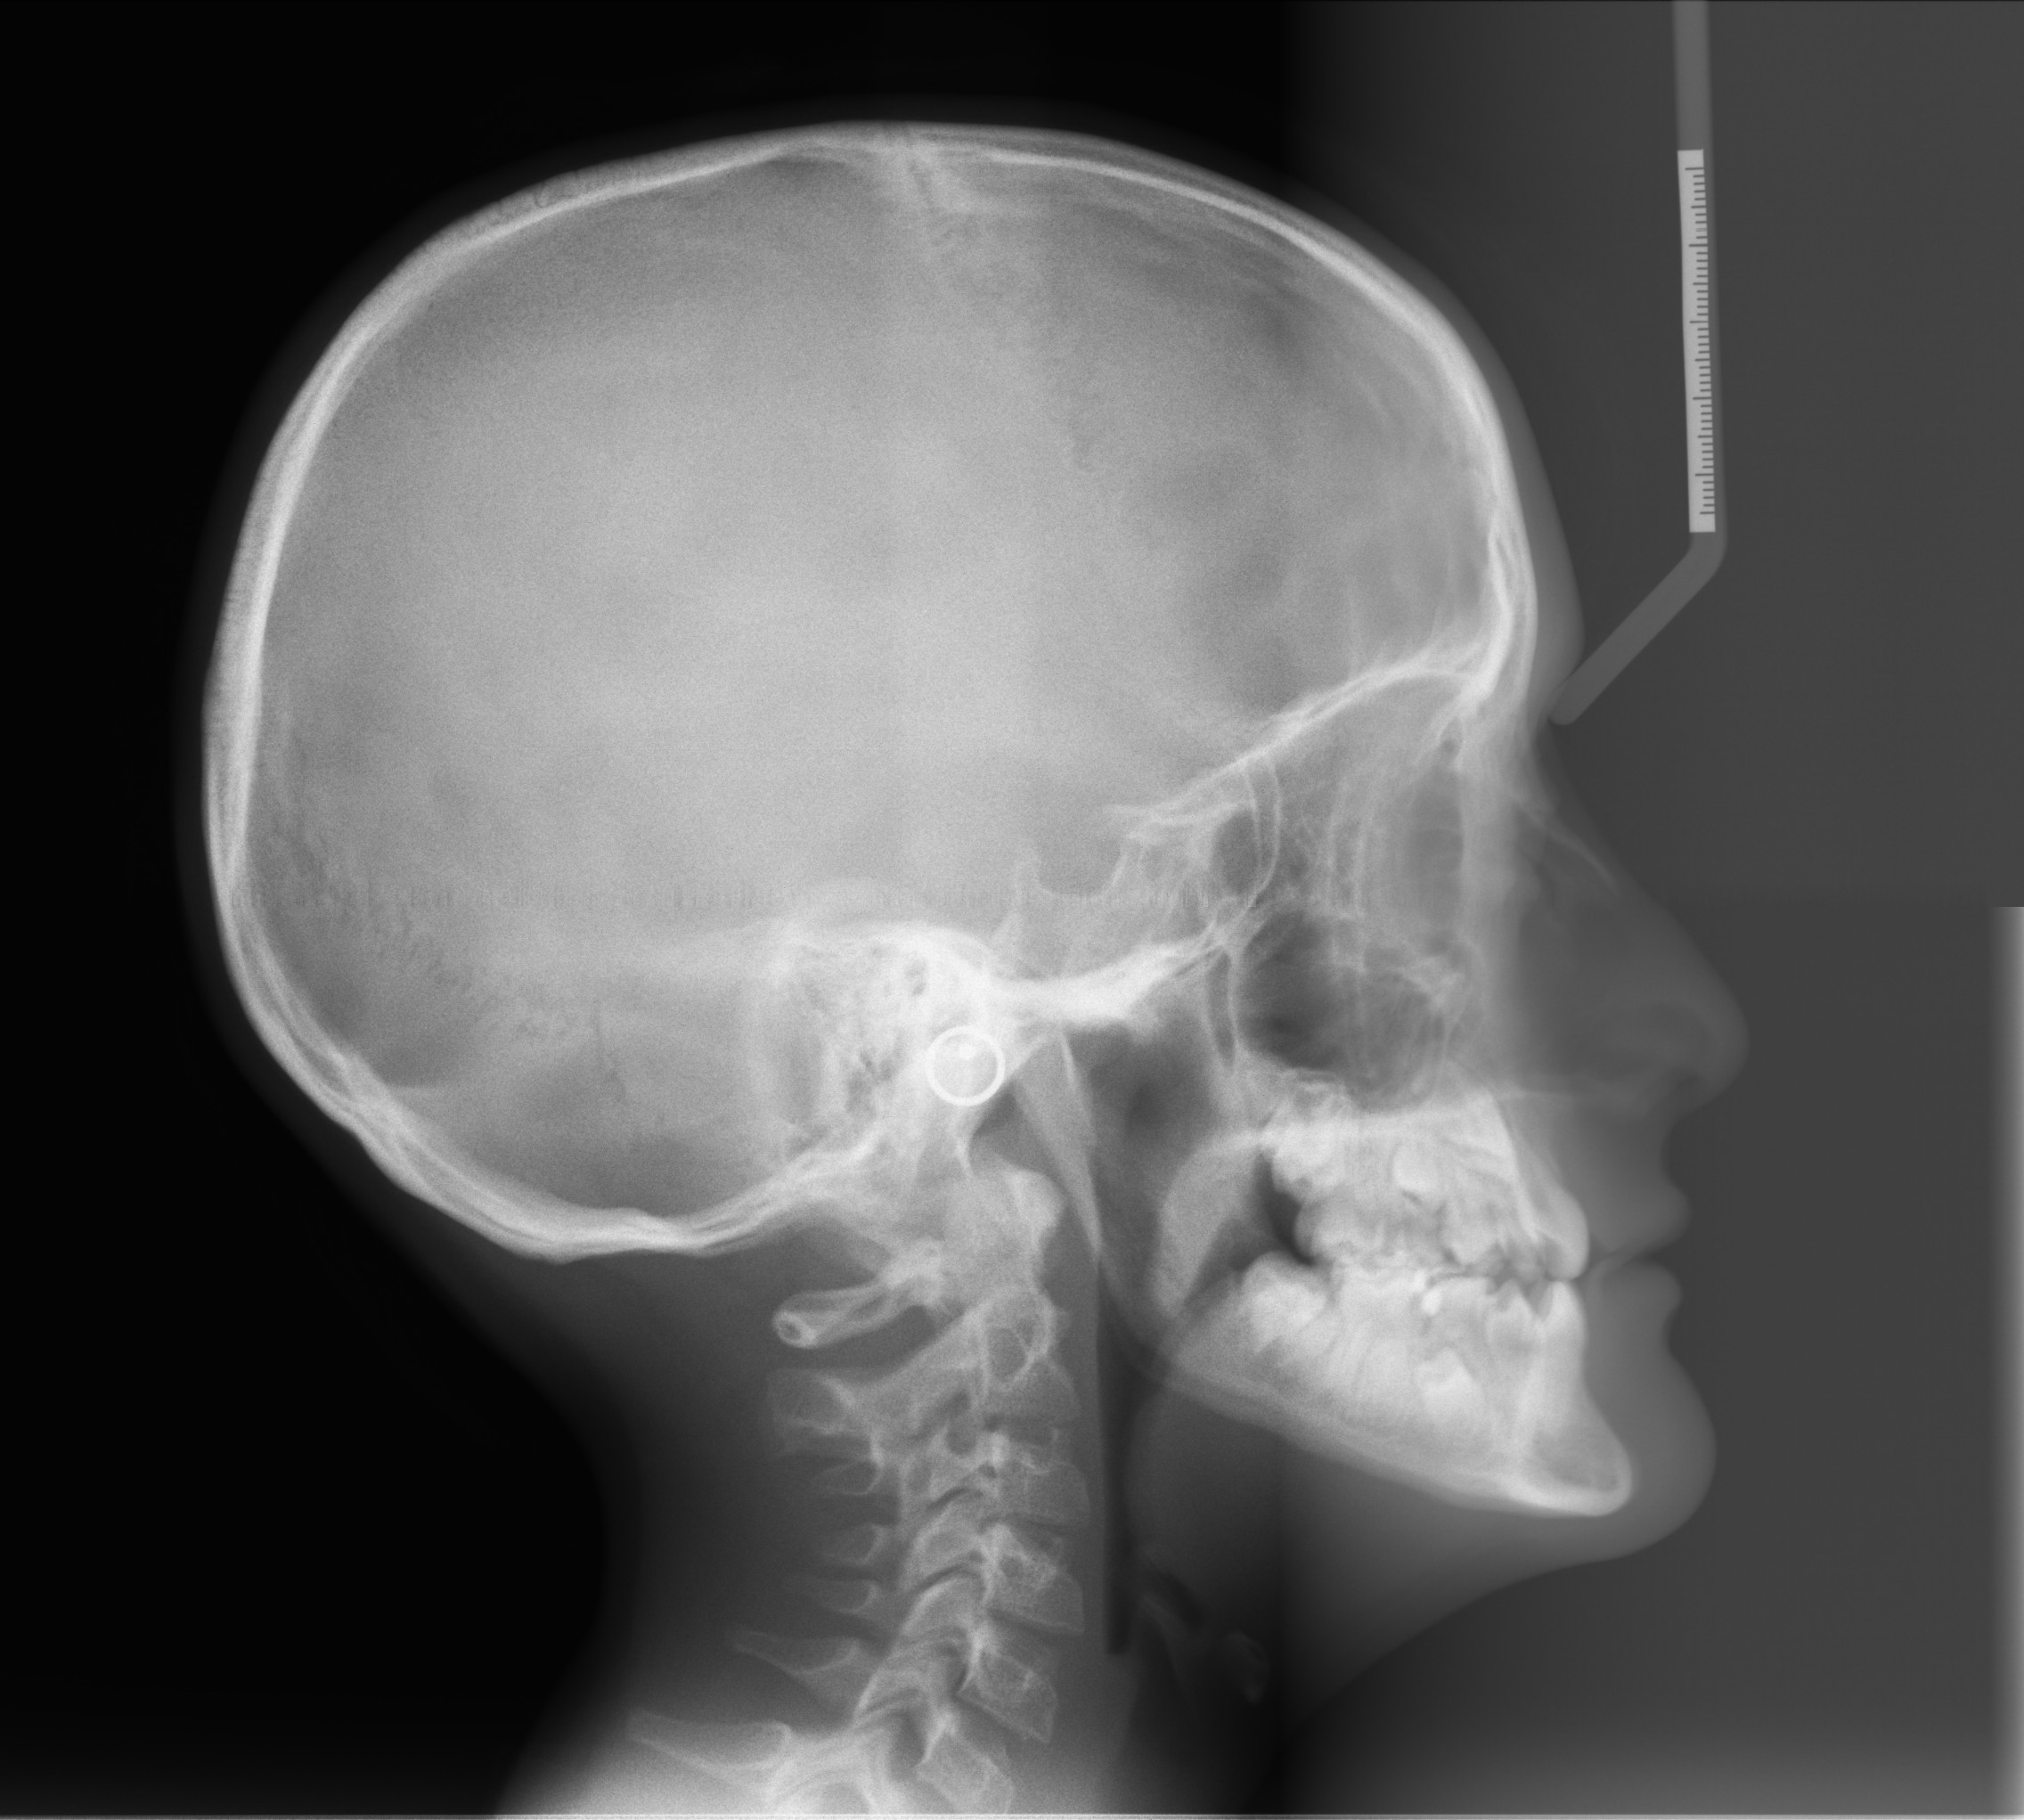

Telecranio

Anche la radiografia del cranio del paziente può risultare determinante.

TELERADIOGRAFIA LATERALE DEL CRANIO, eseguita il 09/11/2018.

Il bambino presenta una malocclusione di terza classe scheletrica.

È un soggetto iperdivergente con tipologia di crescita iperdivergente.

L’incisivo superiore è linguoposto e linguoinclinato.

L’incisivo inferiore è linguoposto e linguoinclinato.